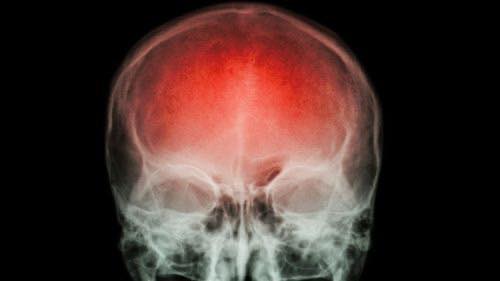

O acidente vascular cerebral (AVC) é uma emergência médica que pode mudar a vida de uma pessoa em questão de minutos. Ele ocorre quando o fluxo sanguíneo para uma parte do cérebro é interrompido ou reduzido, causando a morte de milhões de neurônios por falta de oxigênio e nutrientes. Em um AVC, cada minuto conta: podem morrer até 1,9 milhão de células cerebrais por minuto. Por isso, a detecção precoce e o atendimento médico imediato são determinantes para evitar sequelas graves ou até mesmo a morte.

Na América Latina, a cada 40 segundos uma pessoa sofre um AVC. O episódio pode acontecer em casa, no trabalho ou na rua, o que reforça a importância de reconhecer rapidamente os sintomas. Agir com rapidez pode significar a diferença entre uma recuperação completa e uma deficiência permanente.